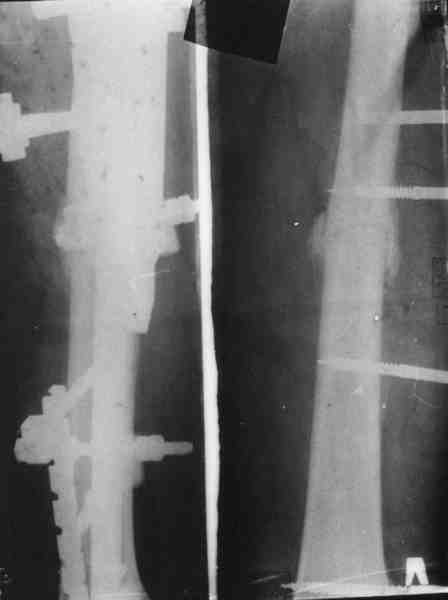

В целом можно поздравить, очень неплохо. Рассверливали ли канал? Вверху вроде один винт, и в динамическом отверстии - лучше бы в статическое, а то стержень можт еще вылезти. А что за стерюень? Похоже на ChM. Из-за того, что выстоит, либо придется удалять рано или поздно. Либо через 2-3 мес. сделать ревизию - извлечь фиксатор, канал немного углубить и рассверлить, и тот же стержень ввести уже поглубже.

В дистальном отделе хватит и одного винта, лучше переднезаднего, чтобы поберечь лучевой нерв.

Канал не рассверливал. Стержень 7мм.ChM. В статическое отверстие не стал вводить винт, побоялся попасть в пустоту, а зря. Лучевой нерв видел,когда вводил дистальные винты. Антибиотики сменены, но складывается впечатление, что они не нужны.

> Канал не рассверливал. Стержень 7мм ChM. В статическое отверстие не

> стал вводить винт, побоялся попасть в пустоту, а зря.

Там есть выкол латеральной стенки, опасения понятны. В таком случае можно стержень повернуть на 90 градусов, чтобы проксимальные отверстия стали передне-задними. Тогда и дистальные винты через направитель можно вводить спереди назад (или сзади наперед).